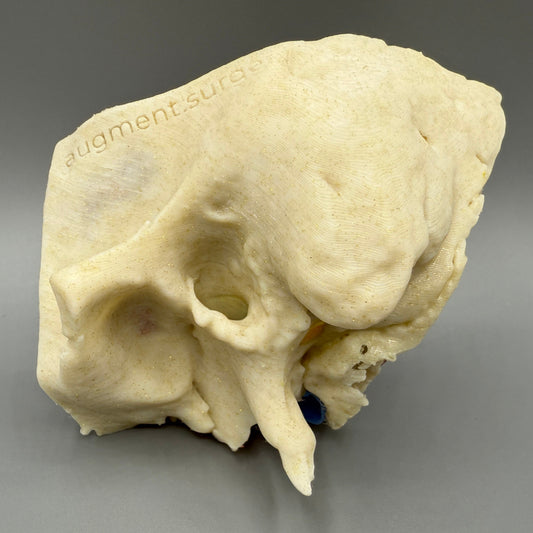

Plant-based surgical simulators made in the U.S.A.

Dissect each one to learn human temporal bone anatomy, hearing and vestibular systems.

Delta-Left OpenEar 3D Temporal Bones

Regular price $74.00 USDRegular priceUnit price per -

Delta-Right OpenEar 3D Temporal Bones

Regular price $74.00 USDRegular priceUnit price per -